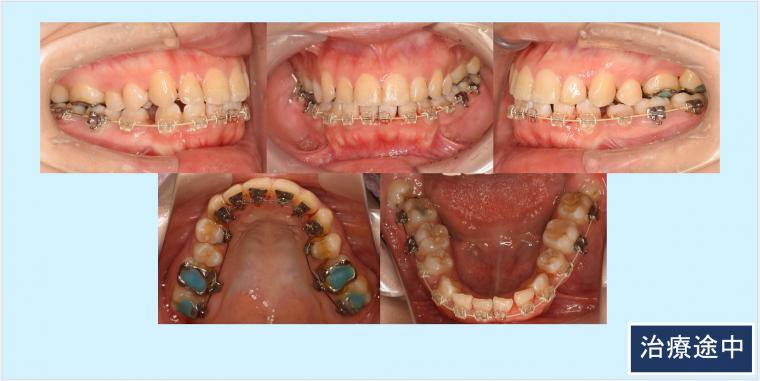

上顎両側5番、下顎両側4番を抜歯して、上下顎前歯部を後方移動致しました。

上顎左側臼歯部の頬側にもブラケット装置を装着し叢生の改善をしました。口元・側貌・スマイルライン共に美しい仕上がりになりました。

◎ハーフリンガル:上顎 カスタムメイド型リンガルブラケット矯正装置(WIN)、セラミックラビアルブラケット矯正装置、下顎 プラスチックラビアルブラケット矯正装置

抜歯部位:上顎両側5番、下顎両側4番